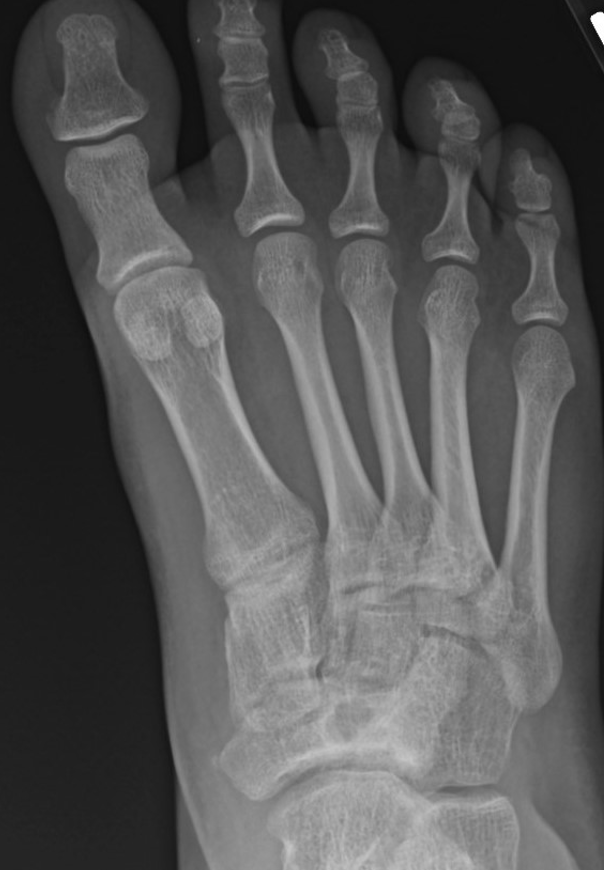

As the Ponseti grew in popularity, I noted significant discrediting of surgical options. Well long-term studies on the Ponsetti are starting to surface, and it is not without its own problems. Kids are lost to follow-up, not braced appropriately, and just like we saw in long-term studies with the posteromedial release, there is a lot of undercorrection. Casting cannot and will not ever achieve what the Cincinnati release can. Although the Ponseti may not have the complications of the Cincinnati, X-ray data reveals that the Ponseti cannot and does not correct everything, most critically, talocalcaneal angles. You can not solve a clubfoot with an Achilles tenotomy and an overly aggressive casting. As these kids develop, I see residual met adductus and calcaneal varus, along with casting complications like flat top talus and met primus elevatus. I then see that they will develop DJD just like posteriomedial and Cincinnati releases. Haasbeck and team in 1997 reported that the Cincinnatti required fewer procedures than the posteromedial release over the life of their study.14 Thomas performed a systematic review in 2019, concluding that the longer the study follow-up, the greater the relapse rate and the poorer the results of the Ponseti.15 For most of us who have done clubfeet surgery for many years, this is no surprise. Among the 46 studies meeting inclusion criteria, they saw as high as 67 percent required future surgeries to address relapse.15

I believe the reason so many surgeons lost faith in the Cincinnati release is due to the multitude of cases that either overcorrected or lost correction. We see teenagers and even recruits showing up with severe calcaneovalgus deformities and even rocker bottom feet as a result of the subtalar and talonavicular releases. But as we studied this, it became very apparent in many cases that these overcorrections were more likely gradual and progressive loss of position as patients were lost to follow-up. Many of my kids looked great at three years of age, but then parents moved. Despite all my efforts to arrange follow-up at their next base or at civilian hospitals, kids were often lost to follow-up. On a few occasions, I was lucky enough to see some of my kids back at eight to 10 years of age. Those X-rays showed complete collapse into valgus. After serious inquiry, you find out that the child stopped wearing inserts after five years of age. Bracing is a necessity, I found, to prevent loss of correction. Although bracing has proven critical for all clubfeet, I find it is much more so for the Cincinnati releases. In reality, this procedure can and does do very well, but not often well enough to meet the rigors of the military or competitive sports.

Here is a typical case presentation. A 21-year-old Marine at Ft. Leonard Wood for training underwent a Cincinnati release at one year old and had stellar follow-up. Her surgeon even wrote her medical waiver for entrance into the Marines. She ran track in high school. She finished boot camp and completed all of her Marine training, but now has chronic pain. She no longer can run. She hasn’t passed her physical training in over a year. She developed talonavicular DJD. By all accounts, her overall clubfoot should be rated an A+; no residual deformity, normal talocalcaneal angles on AP and lateral views, no equinus, no residual varus, only slight met primus elevatus, but no signs of a flattop talus. Clinically, she lacks subtalar range of motion, which I commonly find post-clubfoot release of any kind. So many in the military do very well for a while, but the demands of the military eventually catch up to them. We all root for clubfeet to make it, but the odds are stacked against them.